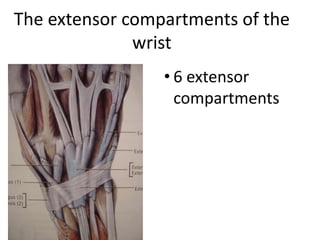

- It describes flexor tendon zones, extensor compartments, and pulley system anatomy.